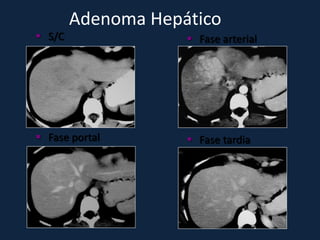

Adenoma Hepático

► s/c: Massa esférica, iso ou hipodensa (devido ao conteúdo lipídico).

Hemorragia: áreas hiperatenuantes intra-tumorais, parenquimatosas

ou subcapsulares.

Pode haver gordura ou calcificações.

► c/c:

– Fase Arterial: Realce intenso (< q na HNF) e heterogêneo

– Fase Portal: Diminuição da atenuação e da heterogeneidade do realce.

– Fase Tardia: Isodenso ao parênquima. Realce não persiste.

 Fase art.    Fase portal    Fase tardia

 S/C                Fase arterial

 Fase portal        Fase tardia